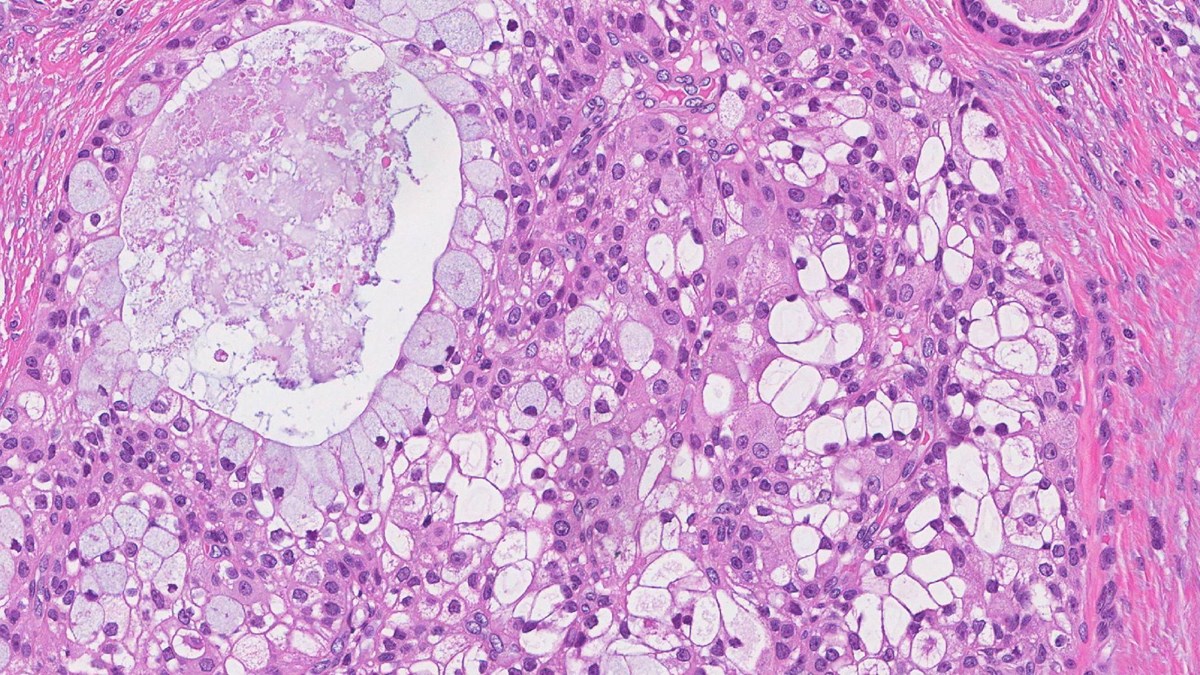

Mucoepidermoid carcinoma (MEC)

Mucoepidermoid carcinoma (MEC) is the most common salivary gland cancer in adults and children (1, 2). The cancer affects more women than men and is most likely to develop in the 40s or 50s (2, 3). The major salivary glands are responsible for producing approximately 95% of saliva and include the parotid (just below and in front of each ear), the submandibular (below the jaws) and the sublingual glands (under the tongue) (4). Minor salivary glands produce the remaining saliva and can be found in almost any part of the mouth (4). Most MEC forms in the parotid gland, although they can also develop in the submandibular and minor salivary glands (2). MEC have been reported at distant sites including the breast, lungs, and thyroid (5-6). MEC typically form a slow-growing, painless lump below the ears, and common symptoms include weakness or twitching in the face, pain or tenderness, ear discharge, trouble swallowing and difficulty opening the mouth (8-10).

Warthin-like mucoepidermoid carcinoma (Warthin-like MEC) is a very rare type of salivary gland cancer that has only recently been identified (14). Warthin tumour is a harmless lump in the salivary gland, which has unique features. The term Warthin-like MEC was given to describe mucoepidermoid carcinoma with features of Warthin tumour (14). There have been very few cases of Warthin-like MEC reported, which makes it difficult to understand who it is most likely to affect (15). All cases of Warthin-like MEC that have been reported have occurred in the parotid gland (just below and in front of each ear) and usually form a painless lump (15).

As Warthin-like MEC is so rare and there are many differences between each reported case, it is very difficult to diagnose. Genetic analysis of Warthin-like MEC has revealed an unusual rearrangement of the MALM2 gene, which can be used to diagnose the cancer alongside examination of cells under the microscope (15).